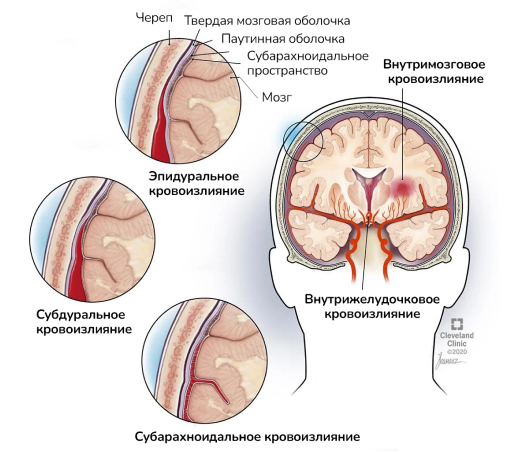

Внутричерепная гипотензия: КТ-исследования и их интерпретация

Раздел: Образы вокруг